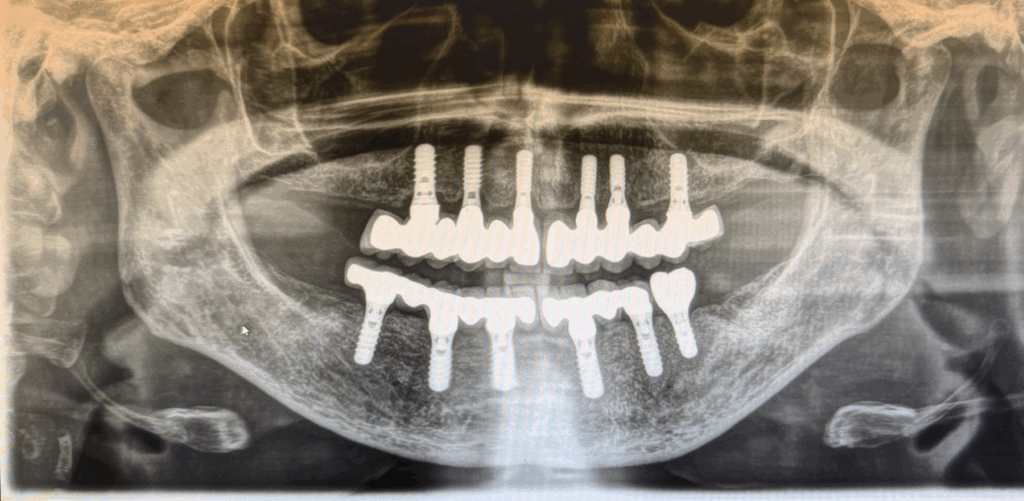

Implant case with Straumann

In cases of advanced periodontitis and severely damaged dentition, modern implant dentistry offers a long-lasting solution.

In this case, the targeted placement of eleven Straumann implants made it possible to provide a complete, fixed restoration — delivering renewed quality of life and a confident smile in everyday life.

Patient (born 1963) with periodontitis and multiple defective teeth in both the upper and lower jaw.

After treatment with eleven Straumann implants (6 in the upper jaw / 6 in the lower jaw) and fixed prosthetics.